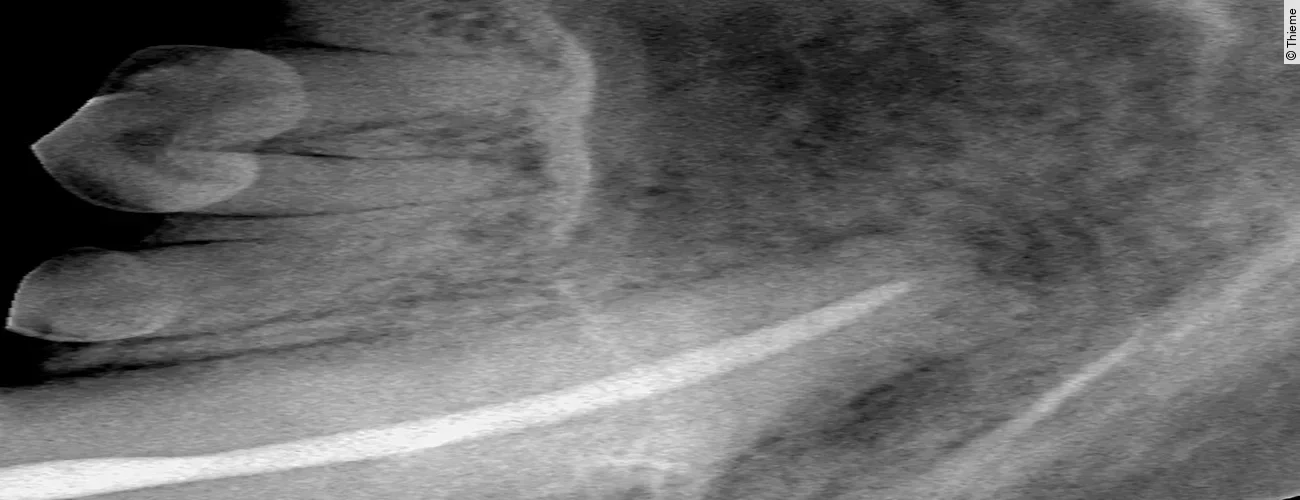

Replantation nach Avulsion Oberkieferfangzahn rechts

Der Originalartikel „Avulsion Oberkieferfangzahn rechts“ stammt aus dem Bild-Atlas der Zahnbehandlungen Hund und Katze; 2. aktualisierte Auflage; 2022.